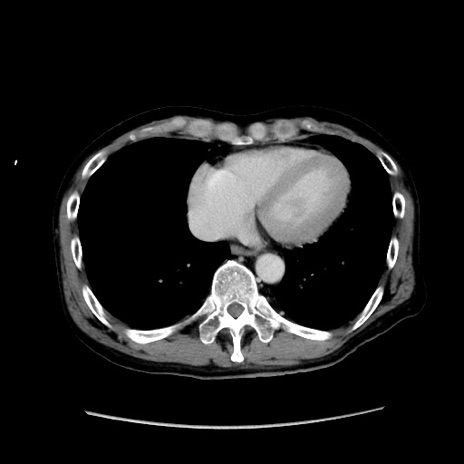

症例37(横断像)

【症例】40歳代 男性

【主訴】腹痛

【現病歴】4時間ほど前に電車に乗車中に臍部上より腹痛出現。徐々に増悪し起立困難となり、救急外来受診。生ものは数日食べていない。今朝お雑煮を食べた。

【身体所見】BT 36.8℃、BP 117/84mmHg、HR 91/min、SpO2 97%、苦悶様、腹部:臍上部広範囲圧痛あり、反跳痛±

【データ】WBC 8100、CRP 0.03